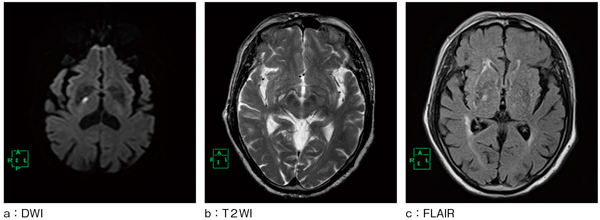

図6は,急性期脳梗塞が疑われてMRI検査を施行した症例である。その際,テンソル撮像を行い,DTI解析を施行した。本症例では,運動路と感覚路の2つの神経線維路の描出を試みた。運動路は皮質脊髄路を起点とし,中心前回を終点としたROIを設定した。感覚路は内側毛帯を起点とし,中心後回を終点としたROIを設定した。このDTI解析結果を,図7,8にそれぞれ示している。運動路にターゲットROIを設定した場合,図8 aに示すように運動路と感覚路の両神経線維が描出された。しかし,図8 bに示すように,感覚路にターゲットROIを設定した場合,脳梗塞部には運動路神経線維の存在は認められず,感覚路神経線維の存在が認められ,神経学的所見と一致していた。今後,ROIの設定場所や解析精度についてさらなる検討が必要となるであろう。

図6 症例(59歳,男性)

左下肢の麻痺にて救急搬送された症例。感覚障害はないが運動障害があるため,急性期脳梗塞を疑いMRI検査施行。右内包後脚領域に急性期脳梗塞が認められる。

図7 DTI解析結果

図8 DTI解析結果